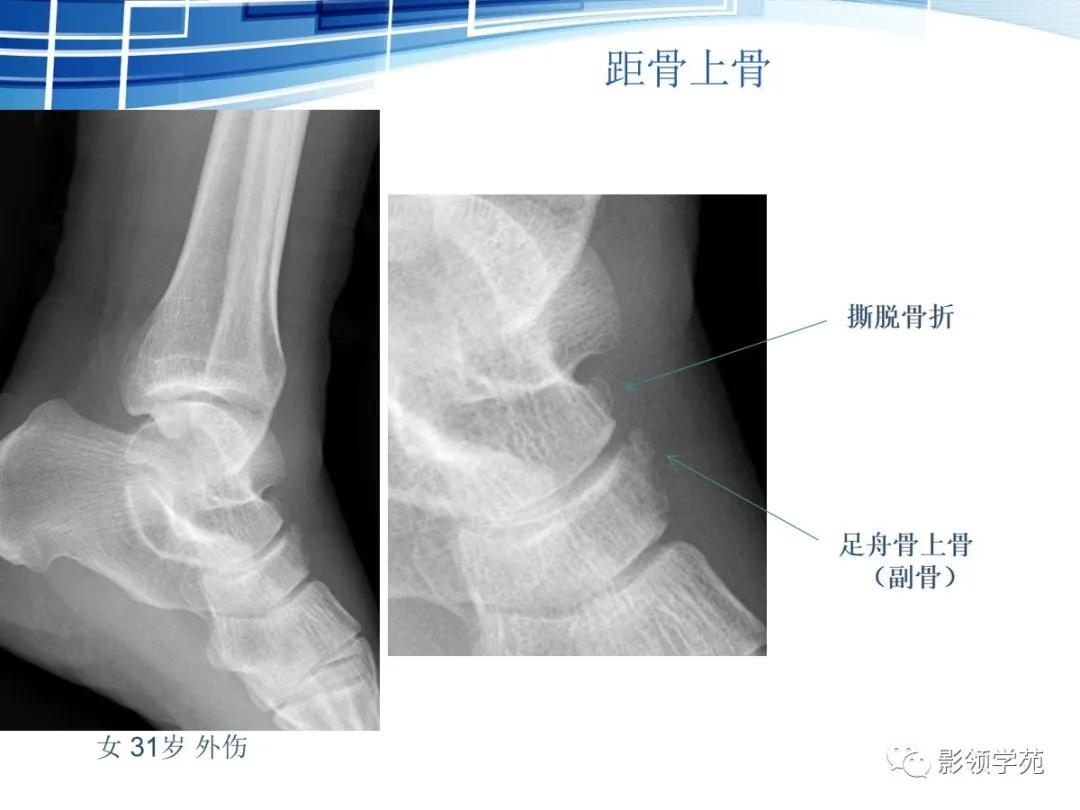

副骨

副骨是由于某一块骨的多个骨化中心在发育过程中没有融合、以致形成多出一块或几块的小骨,也可以是由一个额外的骨化中心发育而来。

虽然撕脱性骨折与永存骨骺、籽骨和副骨在影像学上均有游离的小骨块影的表现,但前者具有骨折的影像学一般特征,而后三者不具有。

永存骨骺、籽骨和副骨的发生与其特有部位及典型特征紧密联系。

常见案例均具有骨块边缘钝圆、骨皮质连续、局部软组织无明显肿胀以及伤后该骨的连续摄片无明显变化等非撕脱性骨折的共同特点。

鉴别重点:独立的骨结构(游离骨)若与相对骨的缺损缘相吻合,是撕脱,如有外伤,更支持。

籽骨、副骨与永存骨骺一般边缘光滑, 周围皮质密度较高, 皮质光整, 附近骨质结构完整, 具有对称性, X线随诊形态及位置不会发生改变, 一般不会引起疼痛。但个别患者由于一些局部肌肉的扭伤而引起副骨的移位, 或由于机械外力的作用使副骨摩擦软组织导致滑囊炎和肌腱炎, 甚至由于长期慢性磨损可与附近正常骨质形成假关节从而产生创伤性关节炎可引起疼痛。而骨折一般具有明确的外伤史, 附近软组织肿胀明显, 疼痛症状明显, 断端锐利, 皮质断裂, 不具有对称性, X 线随诊形态及位置可发生移位。而籽骨、副骨与永存骨骺本身也可在外伤的情况下发生骨折, 但极罕见。